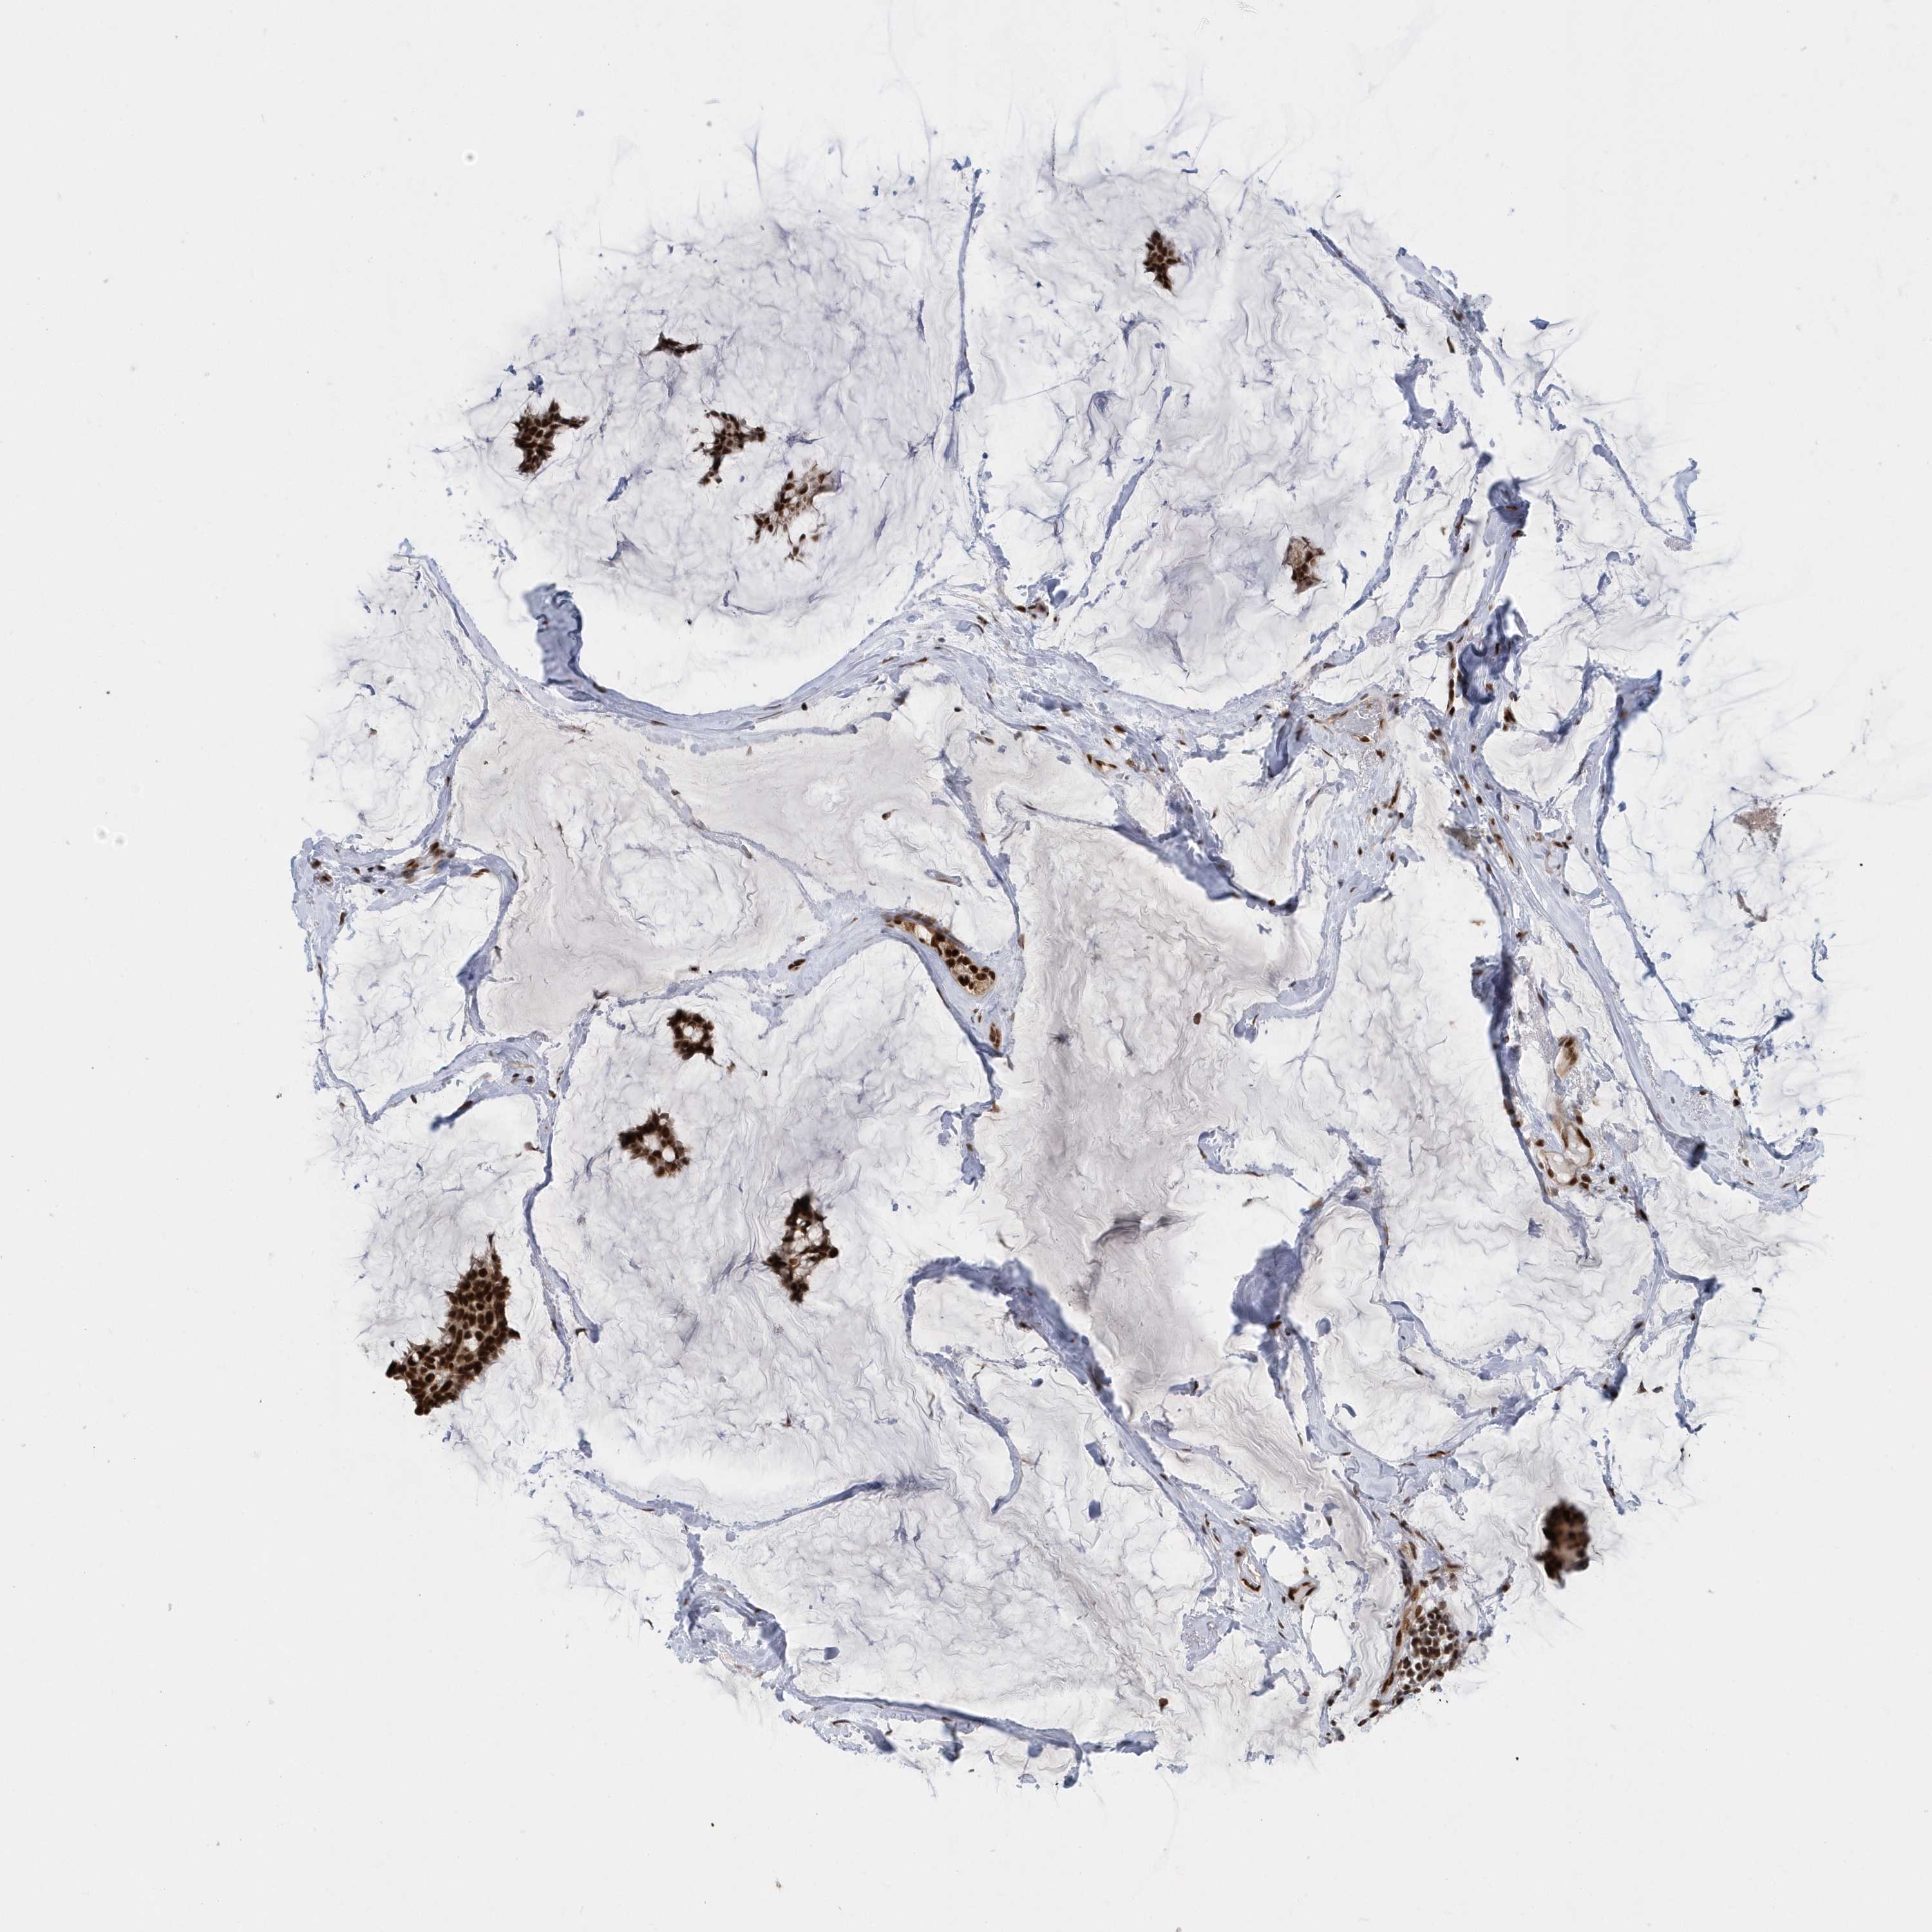

BRCA TCGA BRCA VALIDATION PROTEIN EXPRESSION

ANTIBODIES

AND

VALIDATION